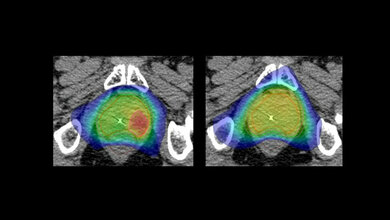

Doch auch bei der Diagnostik geht es mit Riesenschritten voran. Neben den neuen Möglichkeiten in der Bildgebung ist hier beispielsweise Liquid Biopsy ein Schlagwort. Die Nukleinsäureanalytik zum Nachweis von Tumorzellen und Tumor-DNA sorgt für Furore.